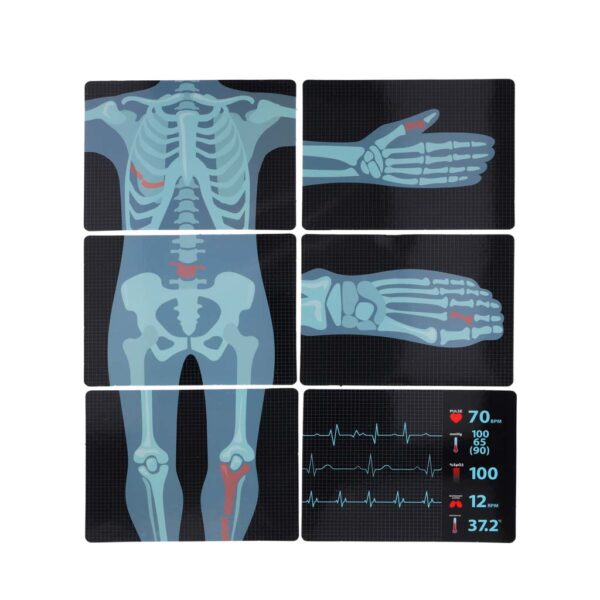

6 rentgena un EKG attēli

Attēlu izmēri: Izmēri: 14,5 cm x 11 cm